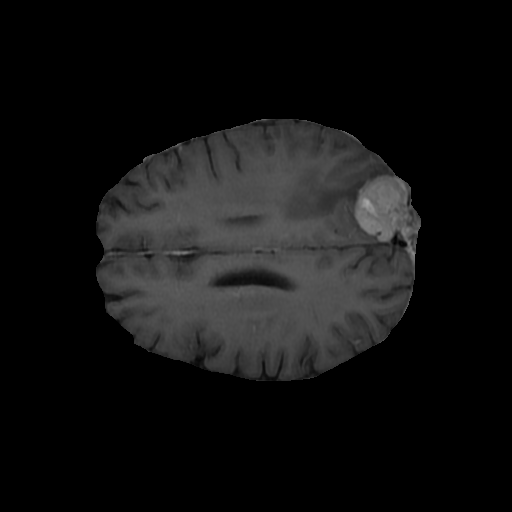

In this current work, extensive experiments have been carried out on Dynamic Susceptibility Contrast (DSC) brain MR images of Glioma patients from TCIA data sets of size using Nvidia RTX 2070 GPU System with high-performance systems with MATLAB 2020a and Python 3.6. The 2D segmented images are processed through a 2D binary circular mask to obtain the brain lesion in the suggested QFS-Net framework. The lesion or brain tumor detection mask is binarized using a threshold of , and in the case of QFS-Net and QIS-Net [39], it is seen that with a radius of pixels, the segmented ROIs perform optimally while compared with the human expert segmented images. Experiments are also performed on two recently developed CNN architectures suitable for medical image segmentation viz., convolutional U-Net [18] and Residual U-Net (URes-Net) [20] available in GitHub. The U-Net and URes-Net networks are rigorously trained using the stochastic gradient descent algorithm with learning rate and batch size allowing maximum epochs to converge. The segmented output images resemble in size with the dimensions of the binary mask and the outcome is considered as tumor region and as background in detecting complete tumor. The pixel by pixel comparison with the manually segmented regions of interest or lesion mask allows evaluating the dice similarity, which is considered as a standard evaluation procedure in automatic medical image segmentation. The evaluation process involves the manually segmented lesion mask as ground truth, and each 2D pixel is predicted as either True Positive () or True Negative () or False Positive () or False Negative ().

Extensive experiments have been performed in the current setup, and experimental outcomes are reported with the demonstration of numerical and statistical analyses using the proposed QFS-Net, QIS-Net [39], convolutional U-Net [18] and Residual U-Net (URes-Net) architectures [20]. The human expert segmented skull-tripped contrast enhanced DSC brain MR input image slices of size and ROIs are provided in Figure 5 as samples. The demonstration of QFS-Net segmented images followed by the essential post-processed outcome on the slice no. for class level with four distinct activation schemes () are shown in Figure 6. It is evident from the experimental data provided in Table LABEL:tab1 that the proposed QFS-Net performs optimally for the -connected quantum fuzzy pixel information heterogeneity assisted activation () with and gray scale set in comparison with other thresholding schemes and gray scale sets under the four evaluation parameters () [44]. The segmented tumors obtained using the proposed self-supervised procedure under class transition levels with four different thresholding schemes , , and are demonstrated in Figures 7- 8 for the class boundary sets and [39], respectively. The segmented images using the remaining two class boundary sets ( and ) [39] are provided in the supplementary materials section. The segmented ROIs describing the whole tumor region after the masking procedure using QIS-Net, U-Net and URes-Net are also reported in Figure 9.